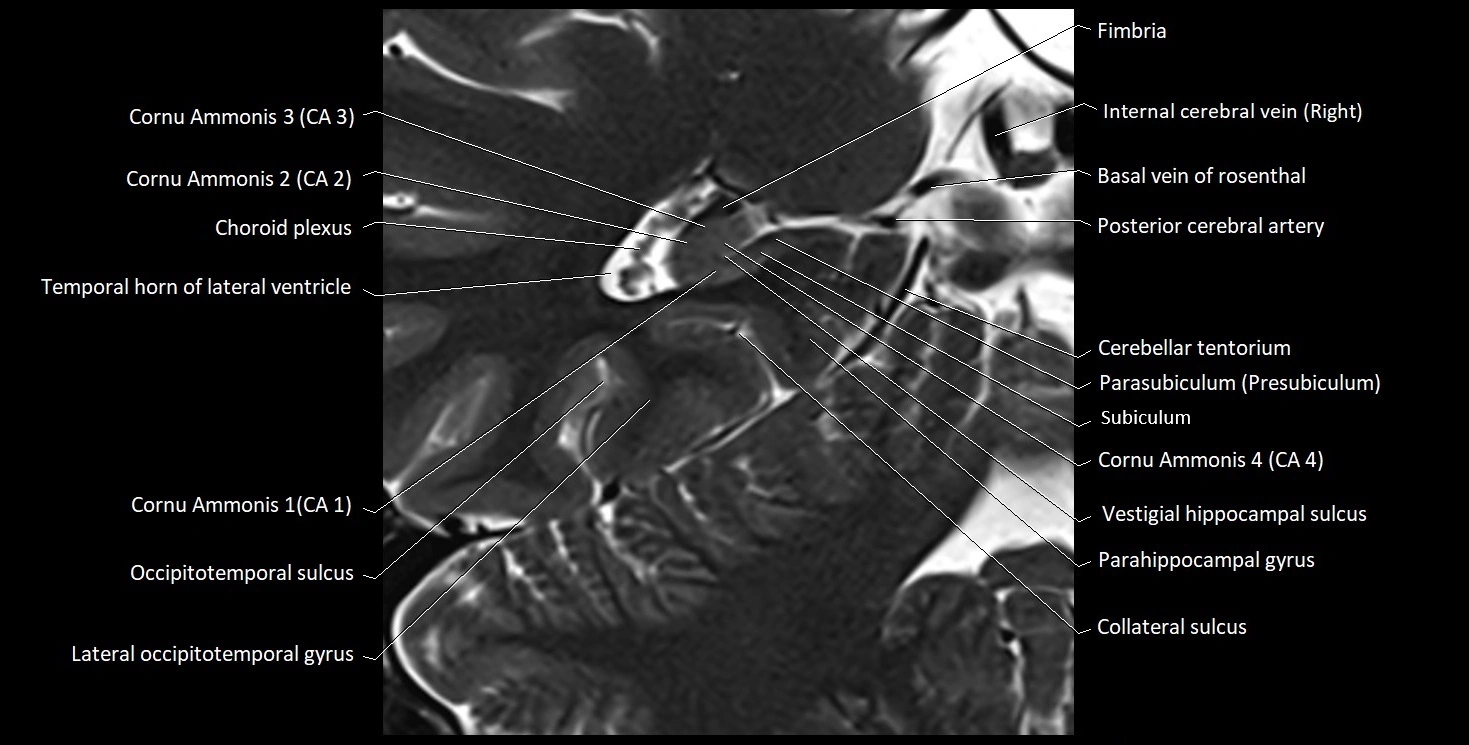

MRI images

image